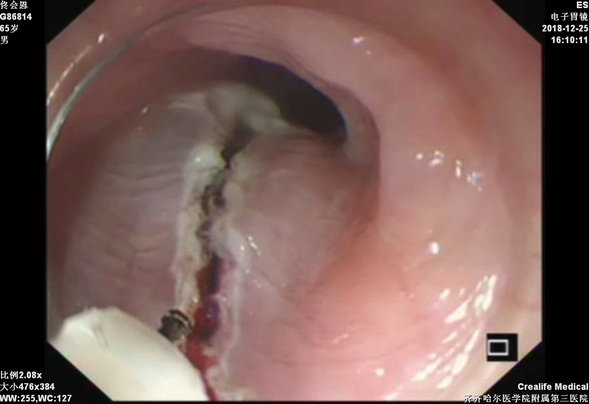

隧道内剥离病灶